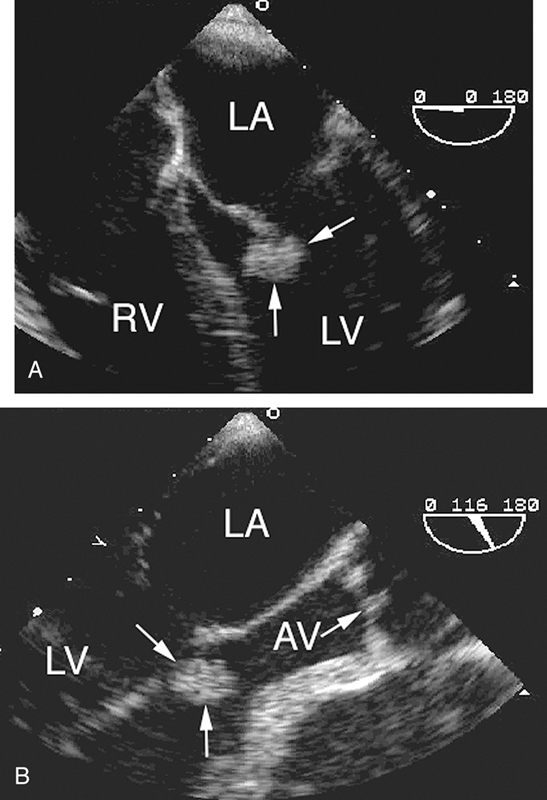

فحوصات تشخيصية لبعض امراض القلب والشرايين التاجية